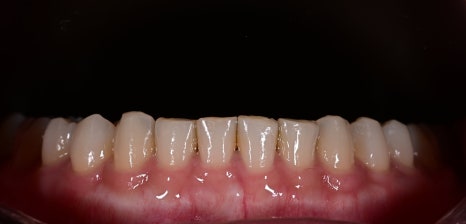

Changes after treatment

After treatment, the patient achieved

brighter teeth

A natural smile

A more polished image

In particular,

they said, “The veneers don’t look obvious.”

Obezero laminate veneers are not simply a treatment that

changes the teeth,

but a treatment that changes the overall impression.